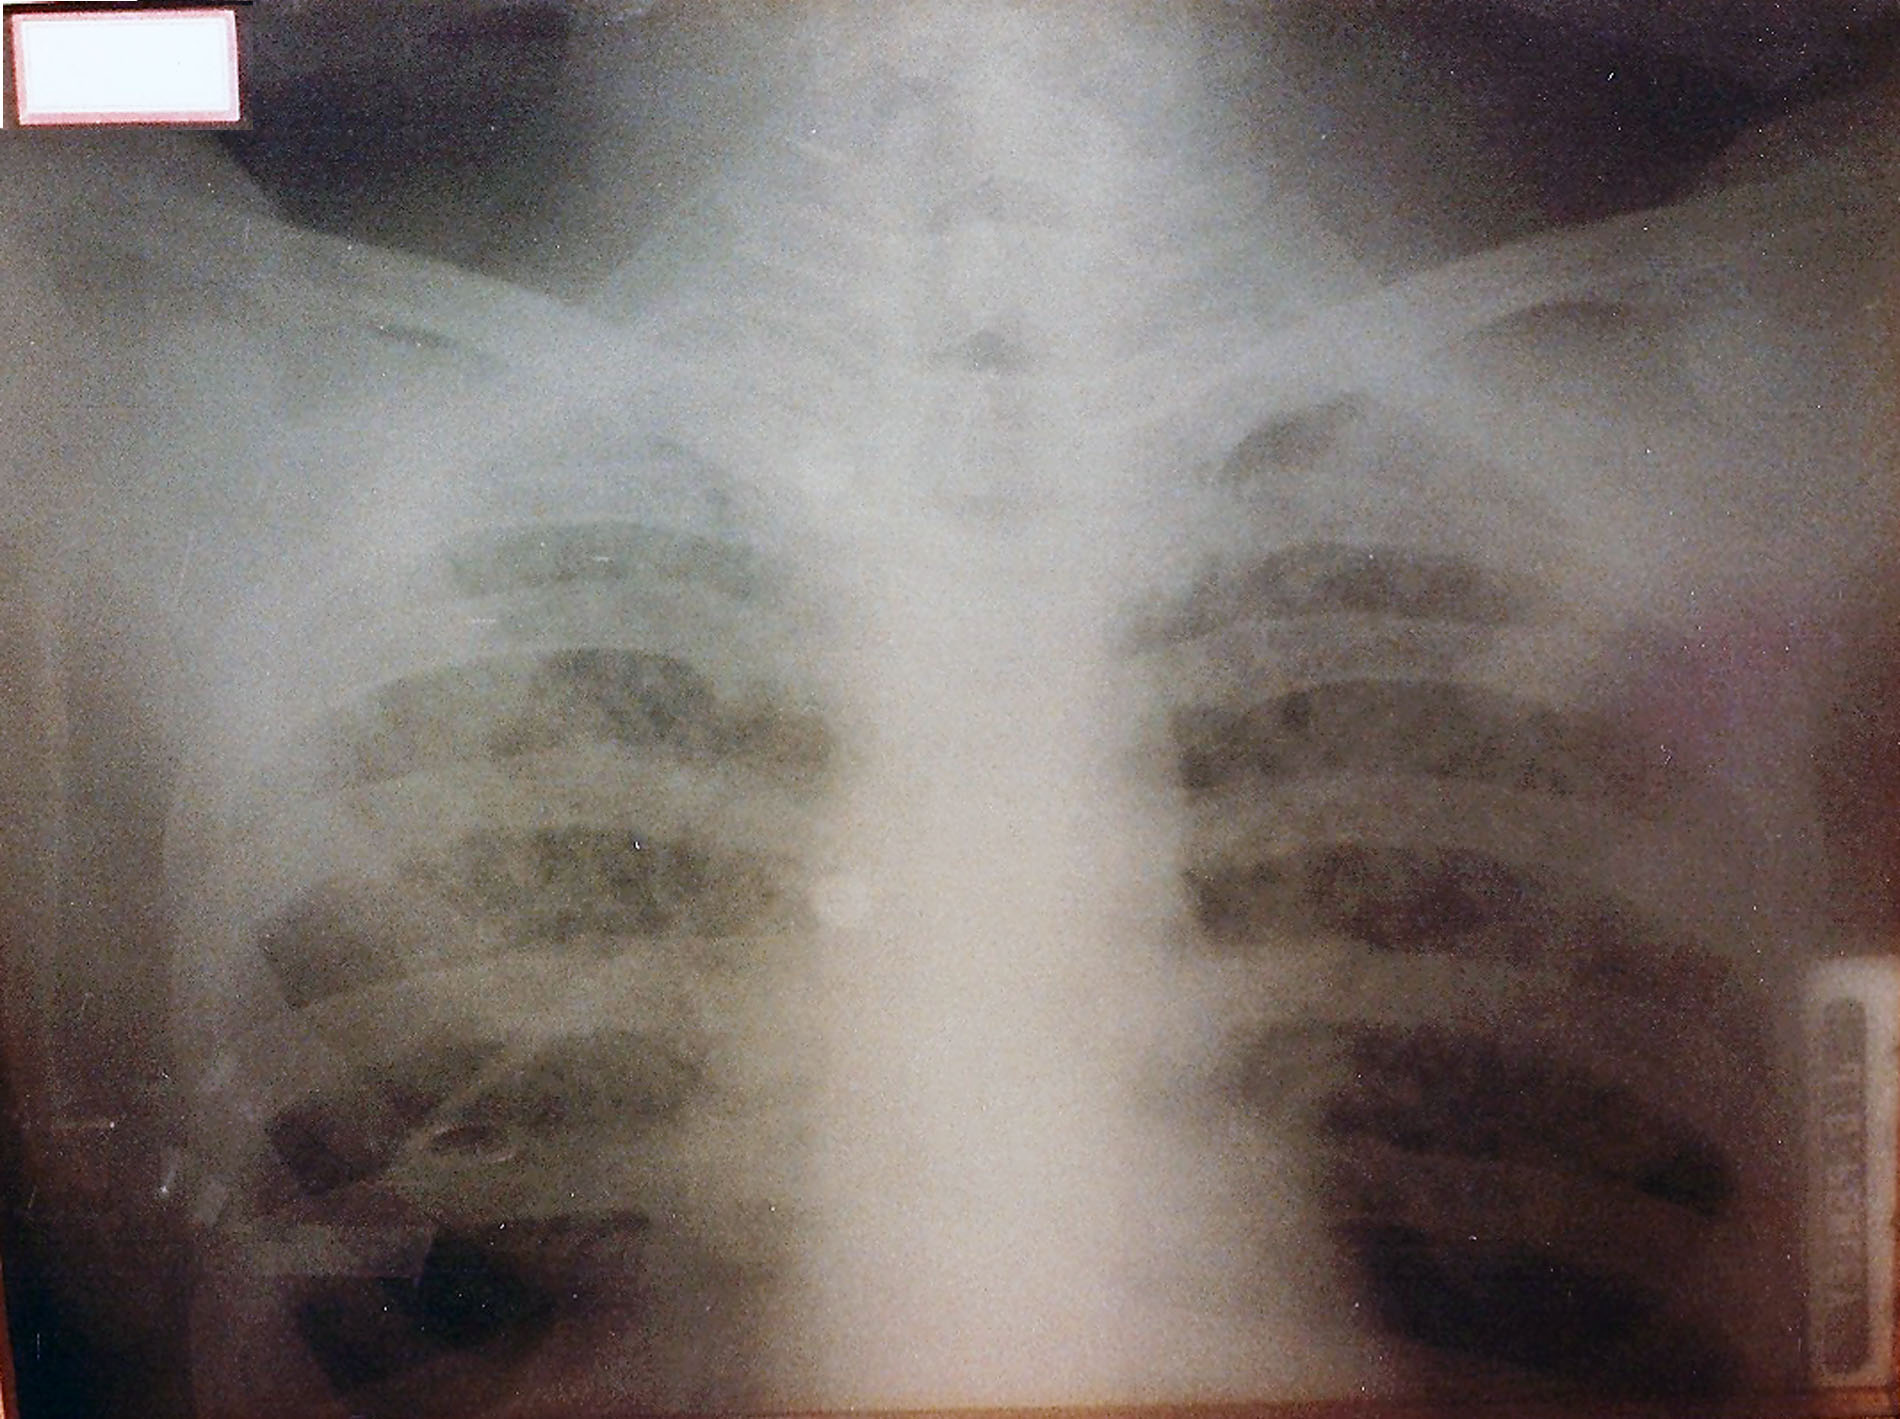

Category: Radiology

Estimated Date: 1920

Name: Glass X-Ray Plate

Manufacturer: Unknown

Description: This chest x-ray of a patient with Tuberculosis from 1920 is printed on glass. The term “flat plate” arose from the original practice of using glass plates instead of film for printing X-Rays. The plate is 11“x 14” and has a paper label indicating a 6 second exposure.